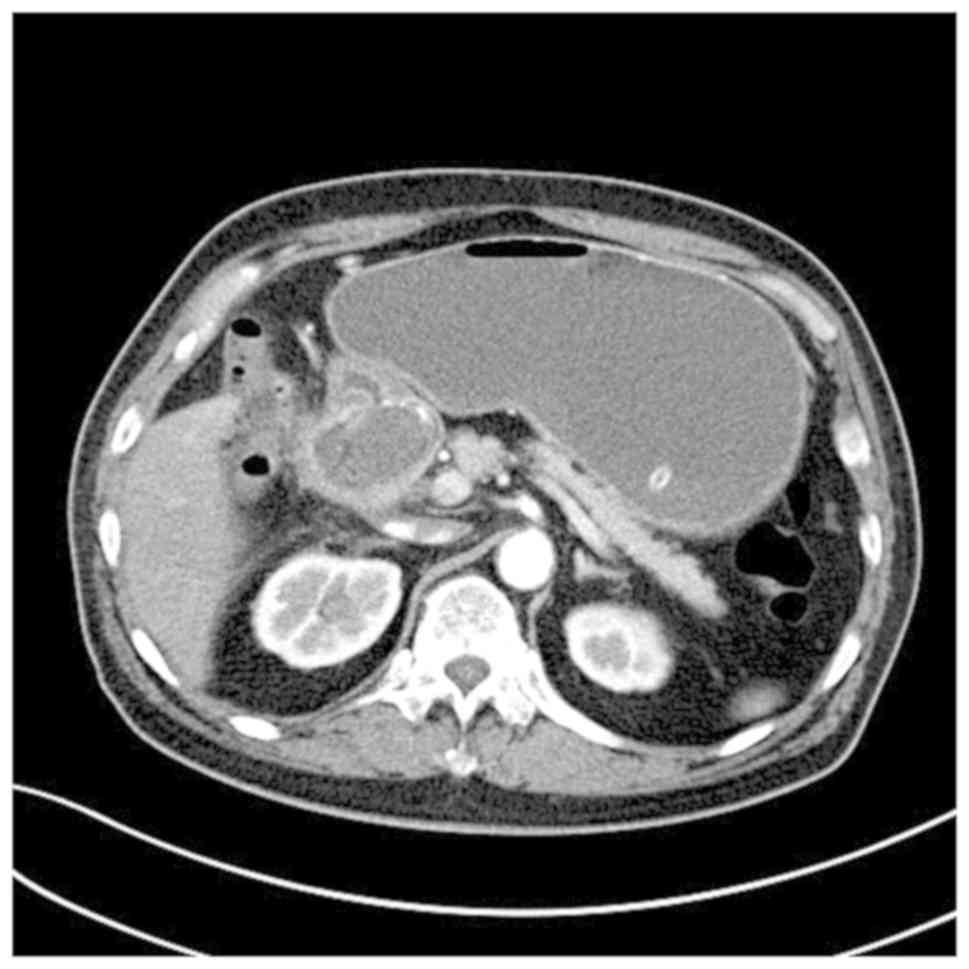

An Unusual Presentation Of Cholecystoduodenal Fistula Massive

Bouveret S Syndrome A Report Of Two Cases El Sorogy M Hanafy Ee

Gallbladder Colonic Fistula An Unusual Cause Of Diarrhoea Bmj

The Korean Journal Of Internal Medicine